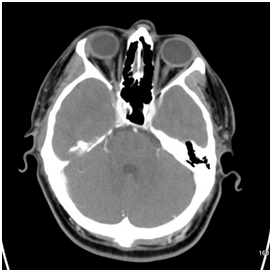

Because branch retinal artery occlusion could not be ruled out, the patient was admitted for the following lab work: complete blood count, Hemoglobin A1C, ANA, lipid panel, RPR/FTA-ABS, HIV, PT/PTT. Imaging was also obtained which included CT (Figure 1) and MRI (Figure 2) as well as echocardiogram of the heart. No imaging abnormalities were found, and there were no abnormal labs besides the positive RPR, including a non-reactive HIV test. When the patient was notified of his positive RPR titer (1:64) with confirmatory FTA-ABS, he returned to the hospital for lumbar puncture which did not reveal any treponemal organisms in his CSF. The patient was initiated on a 14-day course of IV Penicillin, which he completed without complication. The patient’s vision changes have since resolved with no permanent damage noted on funduscopic exam.

Figure 2 MRI brain without contrast.